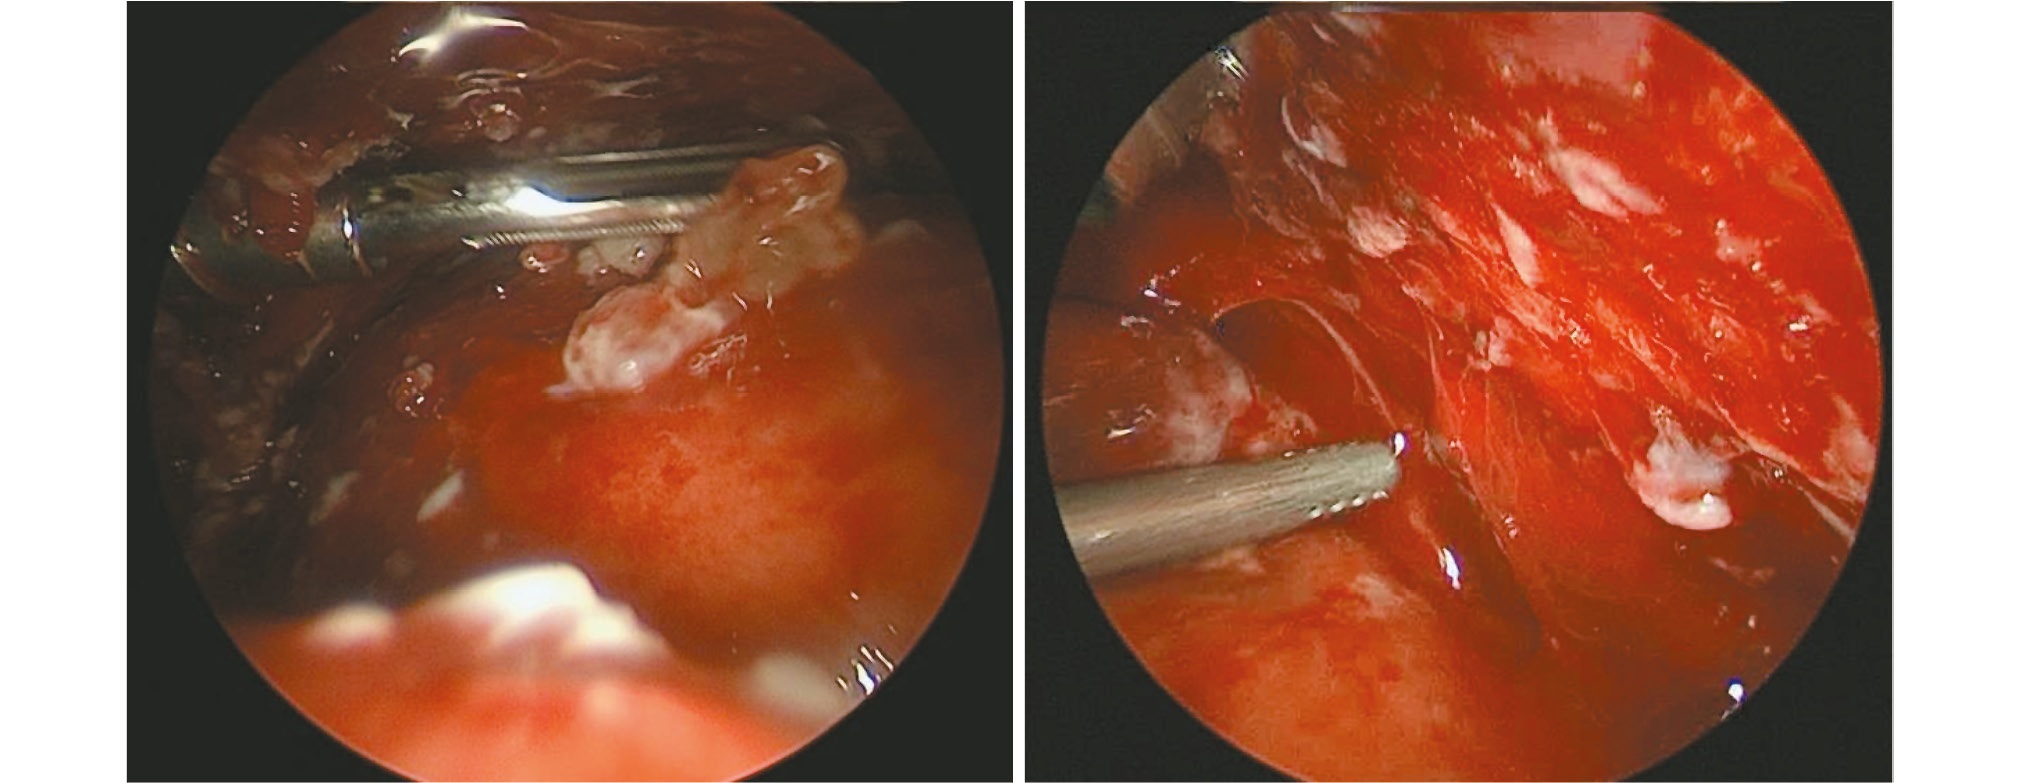

Наиболее демонстративным признаком эффективности применения ПФ послужила динамика рентгенологической картины. Если по критерию реэкспансии лёгкого в 1-е сут после операции значимого различия между пациентами двух групп не выявлено, то рентгенологические признаки регресса фибриноторакса в основной группе констатировались раньше: на (2±0,4) день лечения (рис. 9, 10) и на 3–12 мес. после лечения.

Рис. 9. Рентгенограммы органов грудной клетки больной К., 5 лет (основная группа): a — до операции, b — на 1-е сут после операции; c — на 7-е сут после операции.

Fig. 9. Radiographs of the chest organs of patient K., 5 years old (main group): a — before surgery, b — on day 1 after surgery; c — on day 7 after surgery.